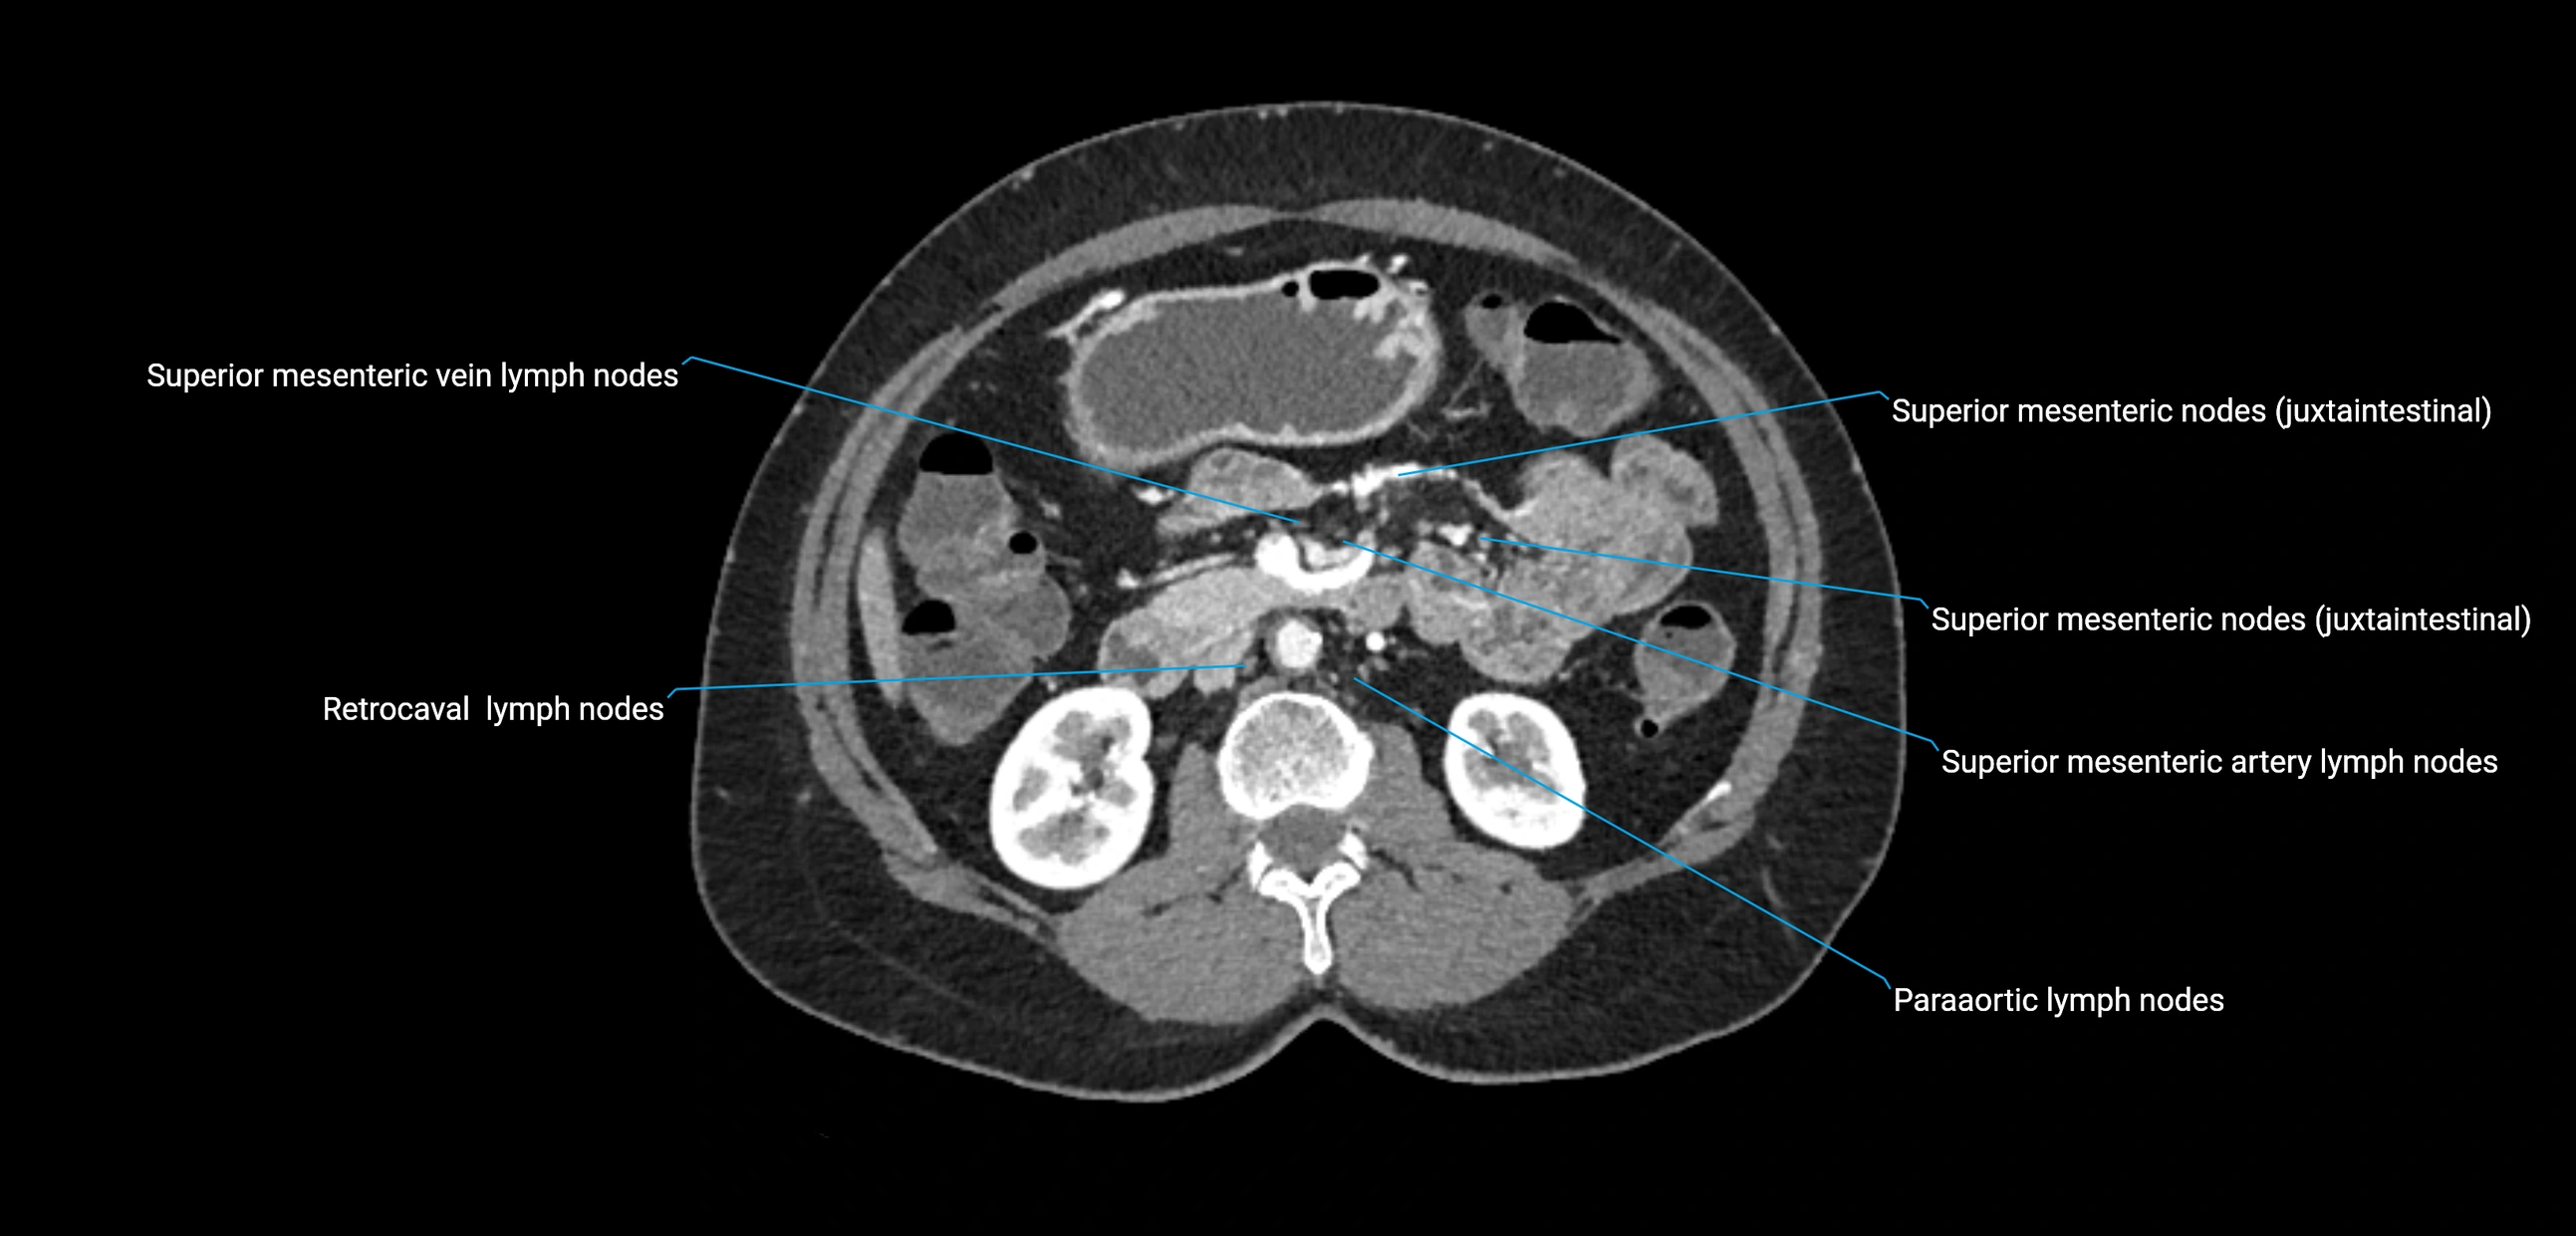

CT Appearance

CT Pre-Contrast:

• Nodes appear as soft-tissue density nodules adjacent to the aorta and IVC

• Calcification may be seen in chronic infections (e.g., tuberculosis)

CT Post-Contrast:

• Normal nodes enhance homogeneously

• Malignant nodes may show heterogeneous enhancement, central necrosis, or conglomerate formation

• Size >1 cm short axis is suspicious, though morphology and distribution are equally important

CT Venography (CTV):

• Demonstrates nodal encasement or compression of adjacent vessels (aorta, IVC, renal veins)

• Useful in staging testicular and ovarian malignancies

• Provides 3D reconstructions for retroperitoneal lymph node dissection planning